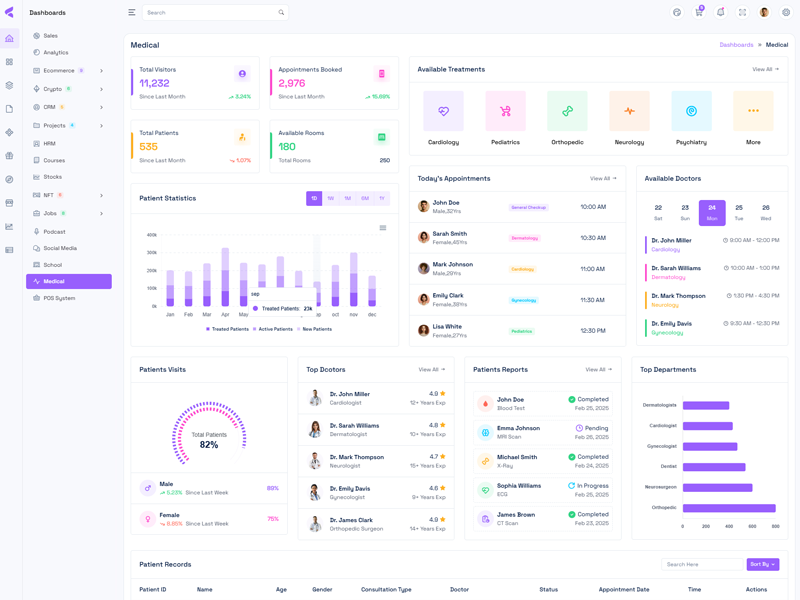

Vyzor Premium Tailwind CSS Admin Template

Vyzor – Create sleek, professional dashboards with ease using this customizable admin template. Skip complex coding with ready-to-use HTML, SCSS, CSS, and JS components. Build stunning, intuitive dashboards in minutes.